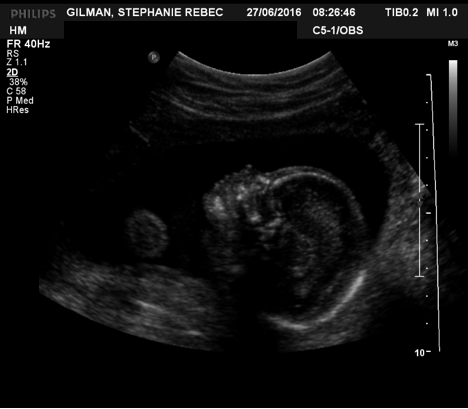

I am currently 28 weeks preggers, or in my 29th week. In some ways, it feels like it has gone fast, and in others, I can barely remember what it was like not to have this little guy in my belly. The due date is November 20th. Whether he presents himself early or late is TBD. Sometimes I feel as though he is already trying to escape and then I tell him firmly, YOU MUST STAY IN THERE LITTLE BABY WE ARE NOT READY FOR YOU and he seems to be a decent listener. So November 20 is the target. Feel free to buy him all his presents before then. (Just kidding, all we want is love and good wishes.) (PSYCH, as if, obviously I want presents, do you not know me at all by now?)